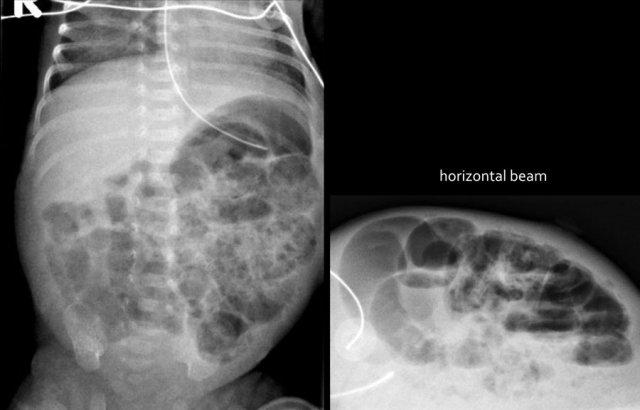

Các hình ảnh cho thấy một trường hợp điển hình của viêm ruột hoại tử với khí trong thành ruột.

Trên hình chụp tia ngang, không có dấu hiệu khí tự do trong ổ bụng.

Đây là hình ảnh của một trẻ sơ sinh phát triển viêm ruột hoại tử.

Ở giai đoạn sớm này, X-quang chỉ cho thấy hình ảnh giãn ruột không đặc hiệu.

Ở giai đoạn này, không thể xác lập chẩn đoán.